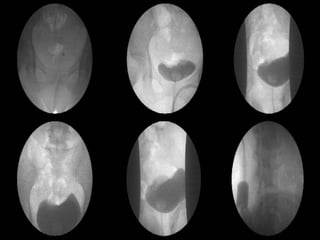

IVP and PV (Day 6) 5 min  15 min

1. Tear of L't renal pelvis or L't upper ureter with  extravasating  of contrast media out to L't retroperitoneal space. 2. L't hydronephrosis and hydroureter. 3. Intact of R't kidneys and its renal calyces, pelvis and R't ureter without dilatation or filling defect found. 4. Well distension of urinary bladder without filling defect found and minimal residual urine.

IVP and PV(Day 6) 5 min 15 min

1. Tear ofL't renal pelvis or L't upper ureter with extravasating of contrast media out to L't retroperitoneal space. 2. L't hydronephrosis and hydroureter. 3. Intact of R't kidneys and its renal calyces, pelvis and R't ureter without dilatation or filling defect found. 4. Well distension of urinary bladder without filling defect found and minimal residual urine.